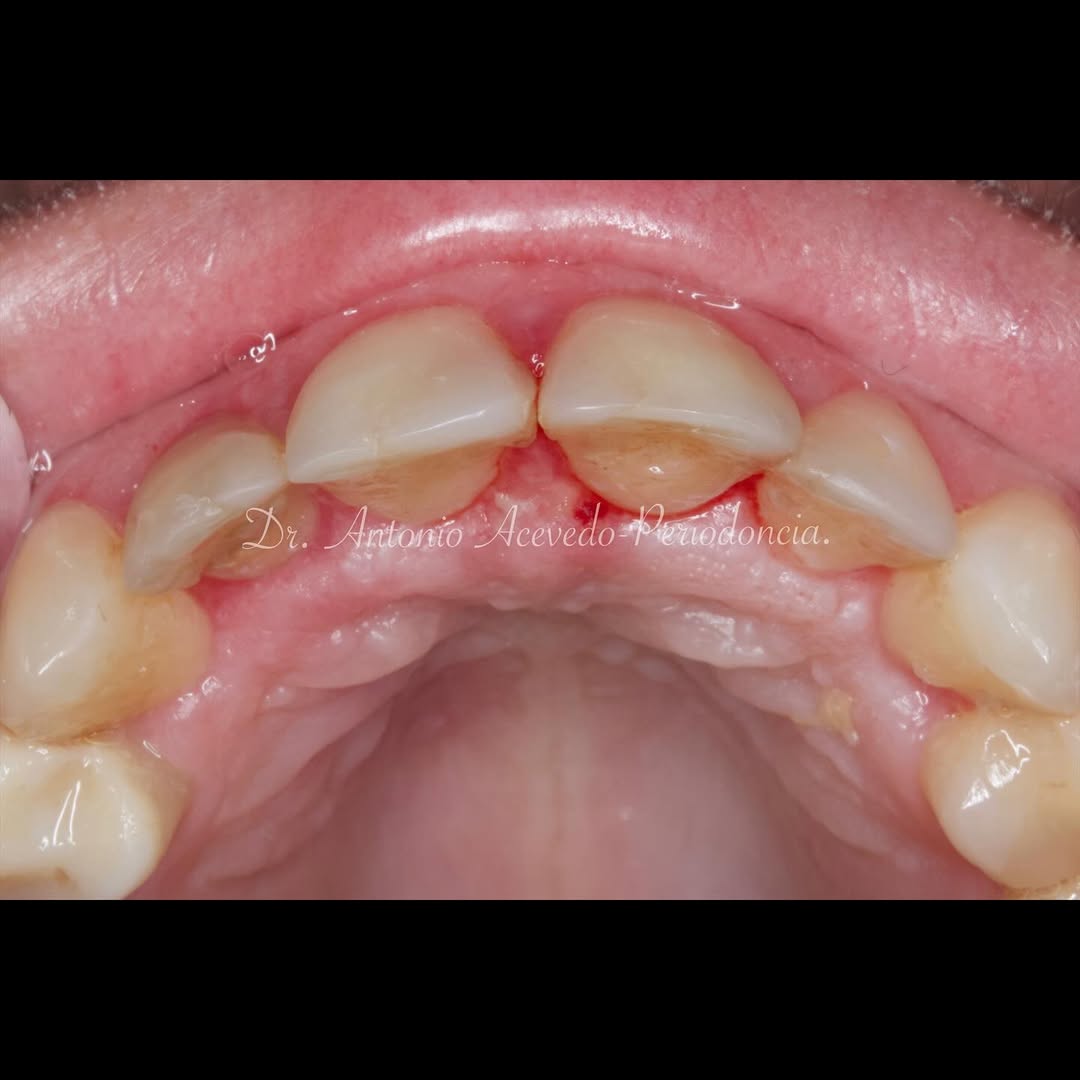

Se presenta un caso clínico de restauración directa en resina composite, ejemplo del valor de la precisión y la técnica meticulosa incluso en procedimientos considerados rutinarios dentro de la práctica diaria. El caso pone en evidencia la importancia del control de la morfología, la textura y la integración cromática, así como del adecuado aislamiento del campo operatorio y la estratificación del material, factores determinantes para conseguir un resultado natural, funcional y duradero. A través de una ejecución cuidadosa, se logró una restauración estéticamente imperceptible y funcionalmente estable, que respeta los principios de mínima invasión y adhesión efectiva. Este tipo de procedimientos, aunque cotidianos, reflejan la constancia y el nivel de exigencia clínica necesarios para ofrecer odontología de calidad en todos los casos, independientemente de su complejidad.